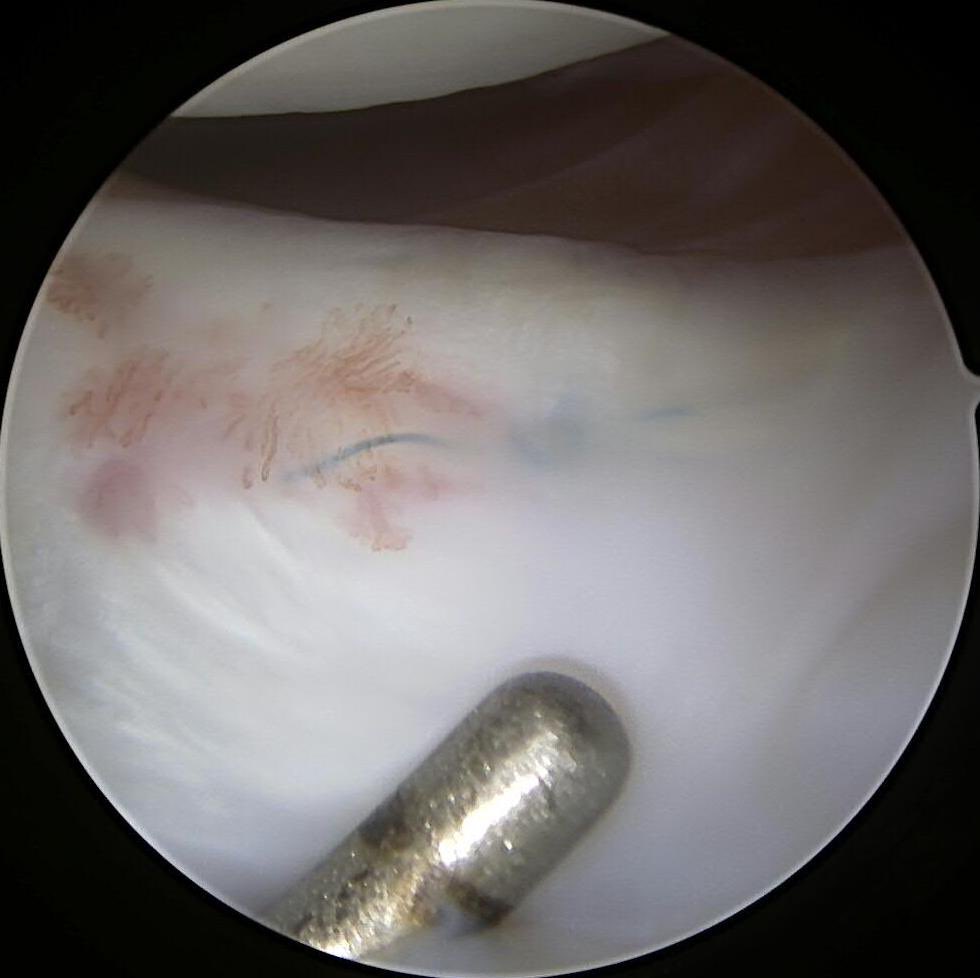

#savethemeniscus LMORT: Lateral Meniscus Oblique Radial Tear- often seen with an acute ACL injury. REPAIR or RESECT?